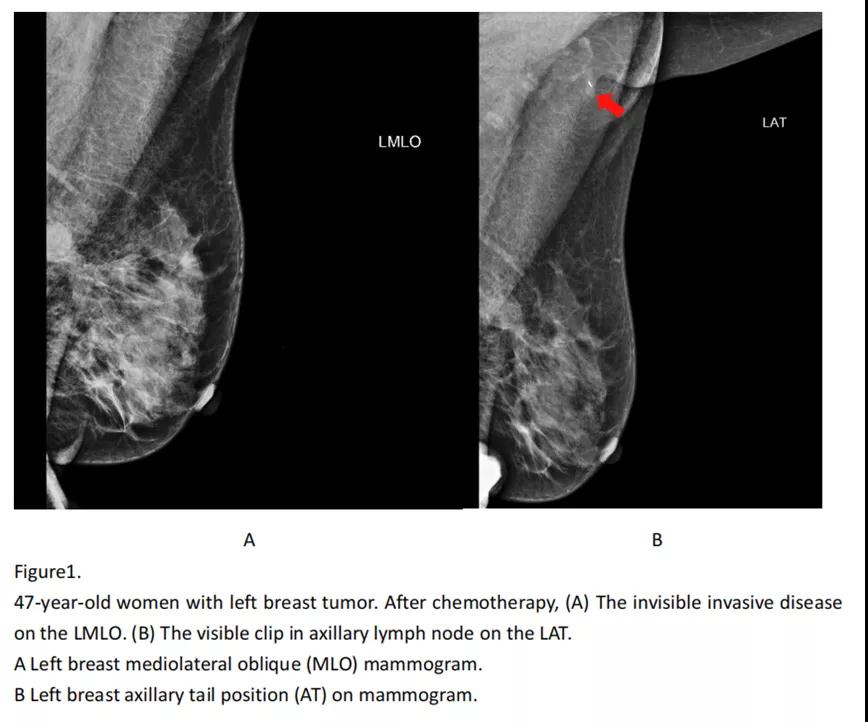

相对于传统的钼钯MLO位,钼钯腋尾位(AT)能更好的显示新辅助治疗后腋窝淋巴结情况,本研究首次将这种特殊的钼钯显像方式结合b超检查以及基线的临床病理资料,构建了一个预测乳腺癌新辅助治疗后非前哨淋巴结状态的模型,其预测效能AUC值高达0.87。该模型能够帮助临床医生在手术前对乳腺癌患者的腋窝情况做出精确的评估,并采用个体化的腋窝手术方式。

■ 研究结论:该临床影像模型纳入因素包括新辅助后的钼钯腋尾位和B超的结果等影像学信息,新辅助后肿瘤大小变化情况以及雌激素受体和HER2表达情况。该模型可以较好地预测初始腋窝淋巴结转移的乳腺癌患者在新辅助治疗后的腋窝情况,帮助临床医生选择个体化的腋窝手术方式。